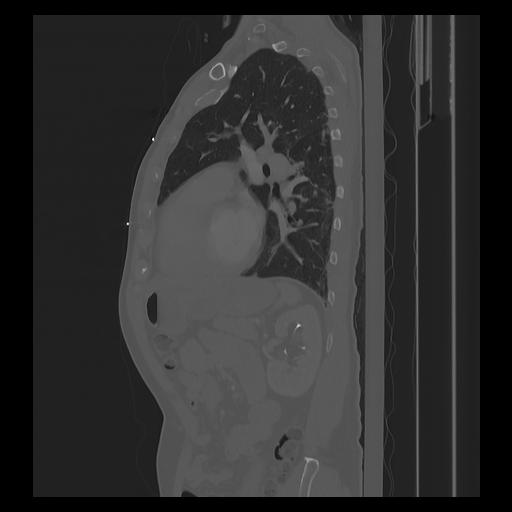

33 PULMON,CE,Sagittal,3.000,PULMON,Sagittal,